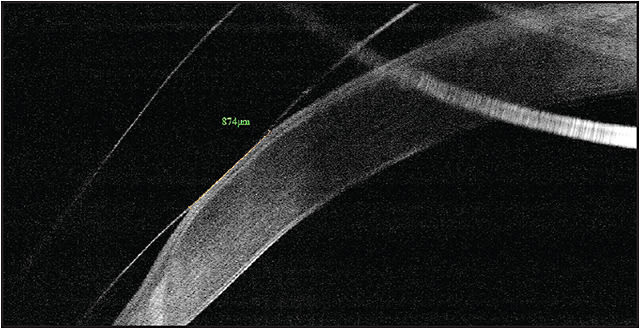

Figure 2. OCT image of the periphery of a scleral lens on a patient who has pellucid marginal degeneration. The lens contacts the cornea over an area 0.87mm long. These types of measurements help guide decision-making in modifying the lens fit and were impossible before the advent of this technology.